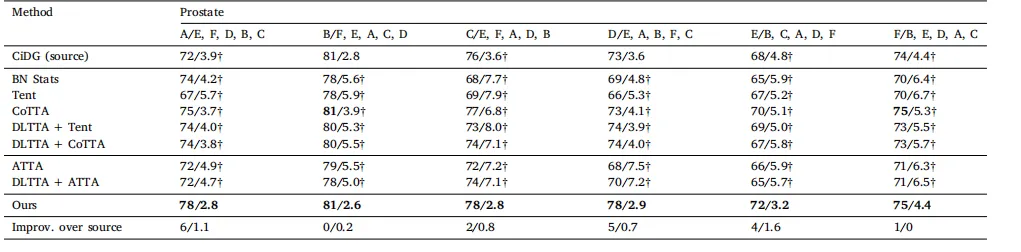

Table 1 Comparison on four datasets. denotes the results obtained by reproduced based on the publicly codes. The best and second-best results are marked in bold and underlined, respectively

表 1 四个数据集上的比较。表示基于公开代码复现所得的结果。最佳结果和次优结果分别用加粗和下划线标注。

Table 2Quantitative evaluation of all methods with CiDG-trained source model on the cross-site prostate task. The adaptation was performed with randomized orders (e.g., A/E, F, D, B, Cmeans the source model was trained on site A and adapted to target domains in order of E, F, D, B, and C, and so on). The same source model (CiDG) was used by all adaptationmethods. Results are shown as Dice (%)/ASSD (mm). The second row shows source/target domains. Source, general, and medical methods are placed into their respective groups.† denotes statistical significance between the Dice/ASSD score of a method and that of our method (𝑝 < 0.05). Best results in bold

表2 使用CiDG训练的源模型在跨站点前列腺任务中对所有方法的定量评估。 适配按随机顺序进行(例如,A/E, F, D, B, C表示源模型在站点A上训练,并按顺序适配到目标域E、F、D、B和C,依此类推)。所有适配方法均使用相同的源模型(CiDG)。结果以Dice(%)/ASSD(mm)表示。第二行显示源域/目标域。源方法、通用方法和医学方法分别归入各自的组别。†表示方法的Dice/ASSD得分与本方法的得分之间具有统计显著性(𝑝 < 0.05)。粗体表示最佳结果。